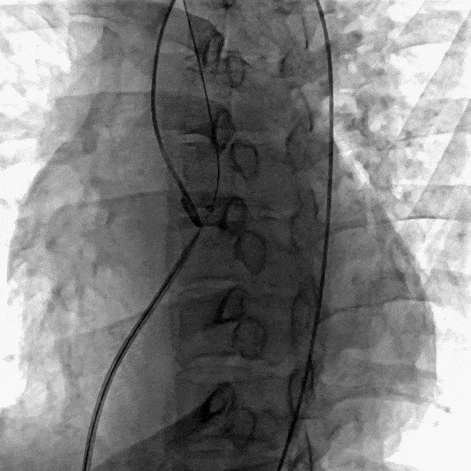

患者局麻后穿刺右股动脉及股静脉,经股动脉送入猪尾导管分别行左心室造影+主动脉根部行根部造影提示主动脉窦瘤破裂(无冠窦-右心房),持续大量左向右分流。明确病变位置后建立股动静脉轨道,经右侧股静脉送入输送鞘并送入先健12/14mm PDA封堵器。再次造影无分流,超声提示窦瘤破裂封堵完好,基本无残余分流,主动脉瓣未受影响。

建立轨道后再次造影证实